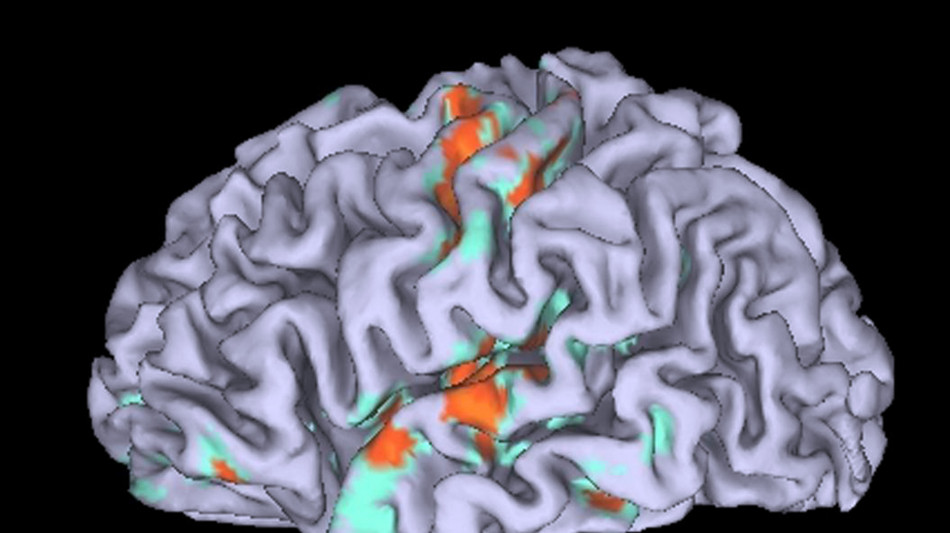

E' in alcune proteine la chiave per capire le differenze che caratterizzano il cervello di ogni individuo: a indicarlo analizzando le differenze del cervello di 98 persone ad ogni scala, dall'analisi delle funzioni fino alle singole proteine, è lo studio pubblicato su Nature Neuroscience sotto la guida di Jeremy Herskowitz, dell'Università dell'Alabama, Chris Gaiteri, dell'Università Suny a New York. Capire il cervello è da decenni una delle più grandi sfide della scienza e un metodo che può aiutare a far luce è quello di scoprire le differenze che esistono tra ogni individuo, sia su scala strutturale - come la forma e la distribuzione dei neuroni - sia a livello molecolare, analizzando le proteine più attive all'interno delle cellule cerebrali. Per far luce su queste possibili differenze i ricercatori hanno analizzato Rosmap, un catalogo di informazioni mediche fatto sui dati di personale cattolico che ha aderito a far parte di un programmo di screening, in particolare suore e preti, con età superiore ai 65 anni e che non presentava problemi di demenza. Si tratta di volontari a cui vengono monitorati ogni anno parametri medici e psicologici e che, inoltre, accettano anche di donare il cervello dopo la morte. Un archivio preziosissimo che ha permesso ai ricercatori di mettere a confronto le funzioni cerebrali di 98 persone de di farlo su scale differenti, dalla risonanza magnetica funzionale alle analisi genetiche, passando dall'espressione delle proteine fino allo studio post mortem al microscopio delle singole strutture cellulari. Un lavoro che ha permesso di comprendere in particolare l'importanza di alcune proteine nello sviluppo delle cosiddette spine dendritiche, una sorta di code dei neuroni e responsabili delle connessioni con gli altri neuroni. Proprio queste differenze, mediate da specifiche proteine, ha un impatto determinante nel definire le differenze tra un cervello e un altro.